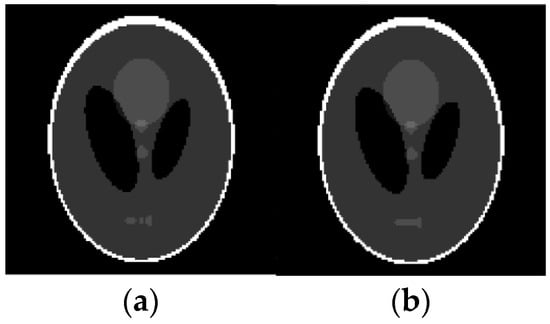

Reconstruction of Shepp-Logan image based on qualitative data. (a) Original image; (b) Reconstructed image.

Figure 9.

For example, these spots can be numerical intervals, and hence we can split the grayscale image into flat layers, corresponding to these intervals. Then one can reconstruct images in the layers independently and combine them again into the entire image. Results of the reconstruction are demonstrated in Figure 7, Figure 8, Figure 9 and Figure 10, where the intensity axes of pixels images were divided into 20 layers. The number of basis squares was about 20,000, and the calculation times were 6–9 min.